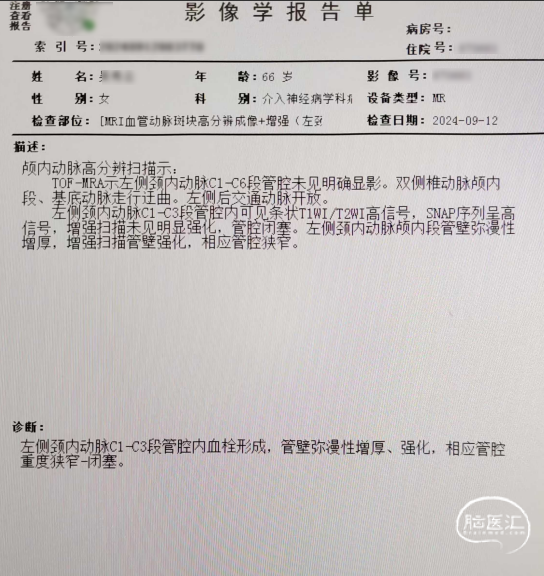

入院颈内动脉颅内段高分辨核磁(2024-09-12)。